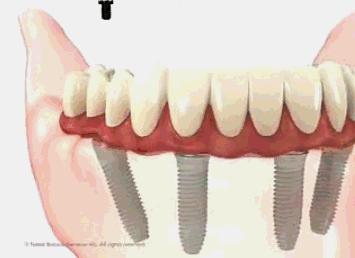

半/全口即刻种植修复技术突破了传统种植牙对牙槽骨条件的限制,针对半/全口无牙患者,通过植入4至6颗种植体达到重建半口牙齿的效果。“半/全口微创即刻种植”这一目前种植牙领域前沿技术,不仅可以减少种植体的植入,降低种植牙修复的风险,为患者节省费用,更重要的是,它同时实现了当天种牙当天就可以戴牙,恢复牙齿的咀嚼功能。